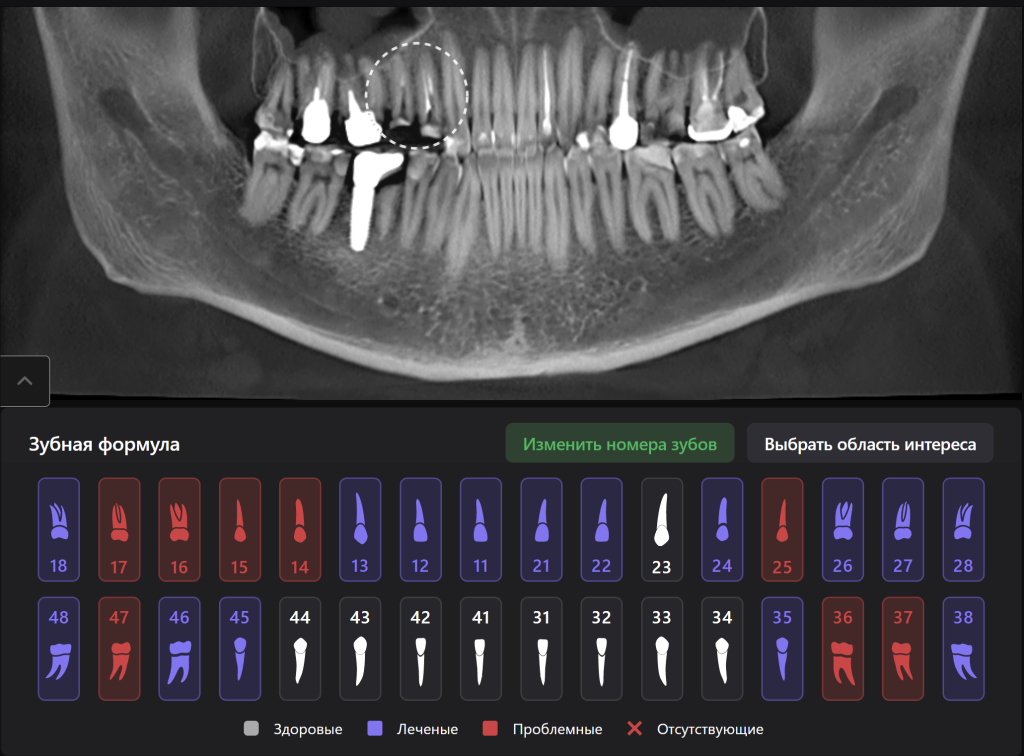

Для принятия клинического решения врач проанализировал данные осмотра и рентгенологического отчета Diagnocat. В отчете содержится оценка ранее проведенного лечения и данные о наличие признаков периапикальных изменений

Обратите внимание на высокий процент вероятности, который предлагает Diagnocat. Принято решение о сохранении зубов и проведении повторного эндодонтического лечения